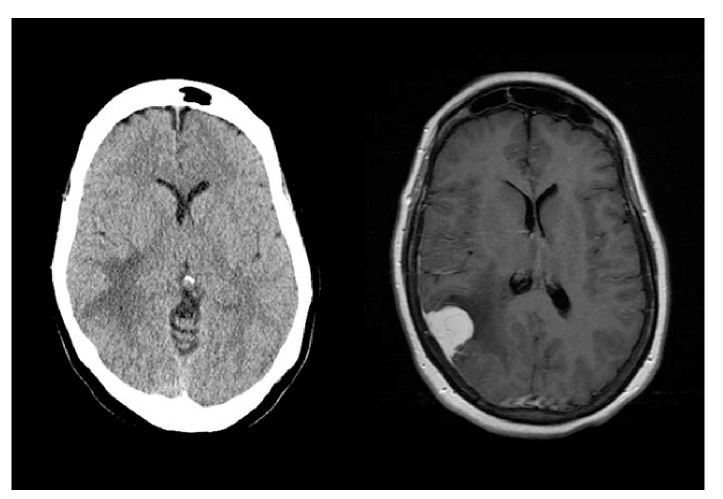

What imaging modality is used? -what abnormalities are seen?

A

-left: noncontrast CT, brain, axial, brain window; right: IV contrast enhanced MRI, brain, axial, T1 weighter -left: edema; right: tumor and edema (R pariteal meiningioma)